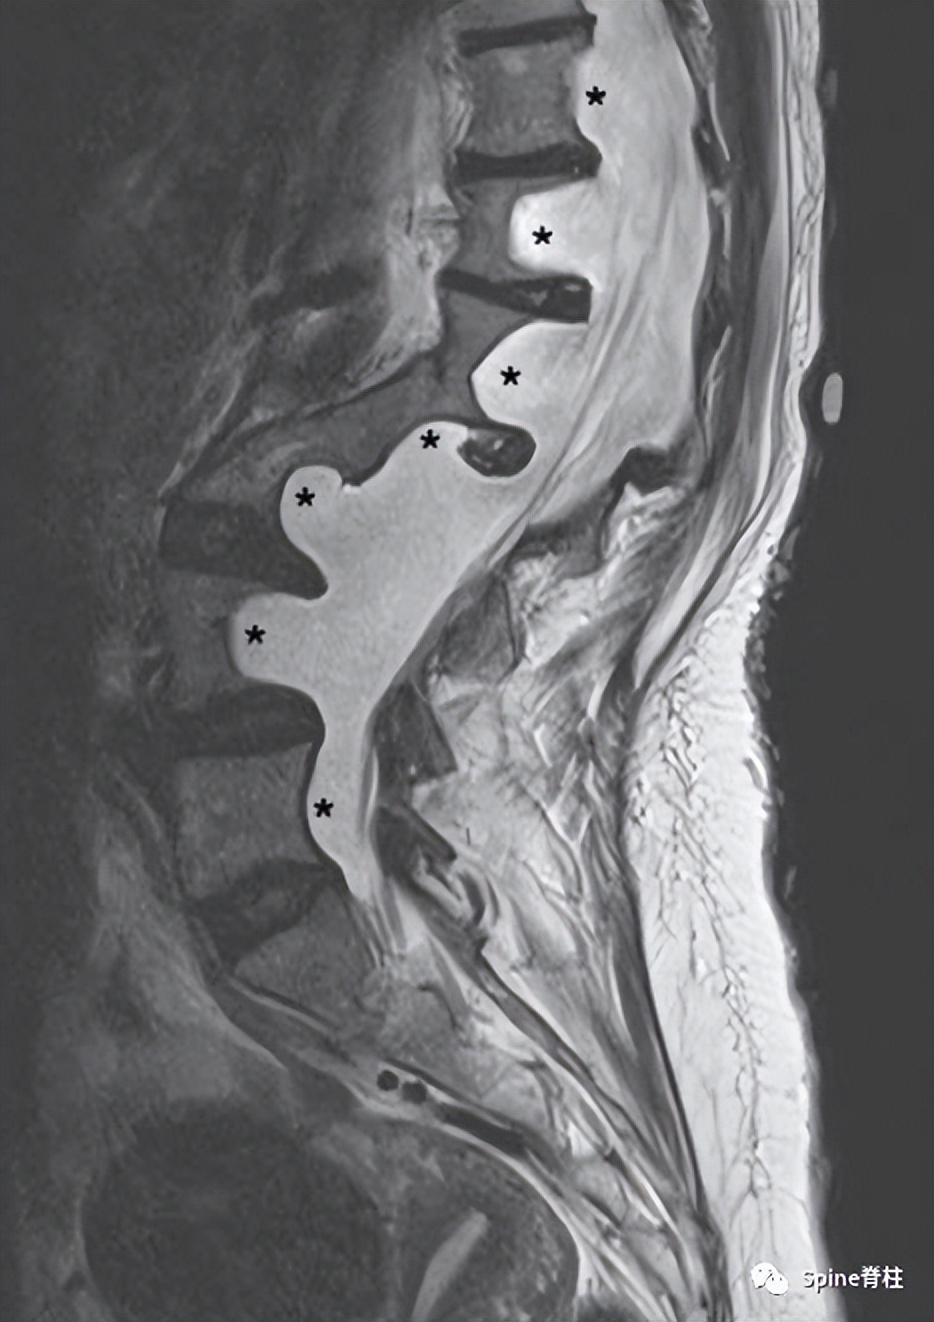

一位43岁1 型神经纤维瘤病女性患者,腰骶椎矢状位T2加权像提示硬膜扩张引起的椎体后壁扇形凹陷(星号) PMID: 20624860